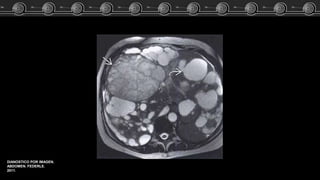

Malformacion A-V?? CasoClínico Las MAV pueden estar ocasionadas por trastornos hereditarios que ocasionan displasia fibrovascular. Grandes arterias tortuosas intra y extrahepaticas. Realce heterogéneo del parénquima hepático. Pueden simular masas. DIANOSTICO POR IMAGEN. ABDOMEN. FEDERLE. 2011.